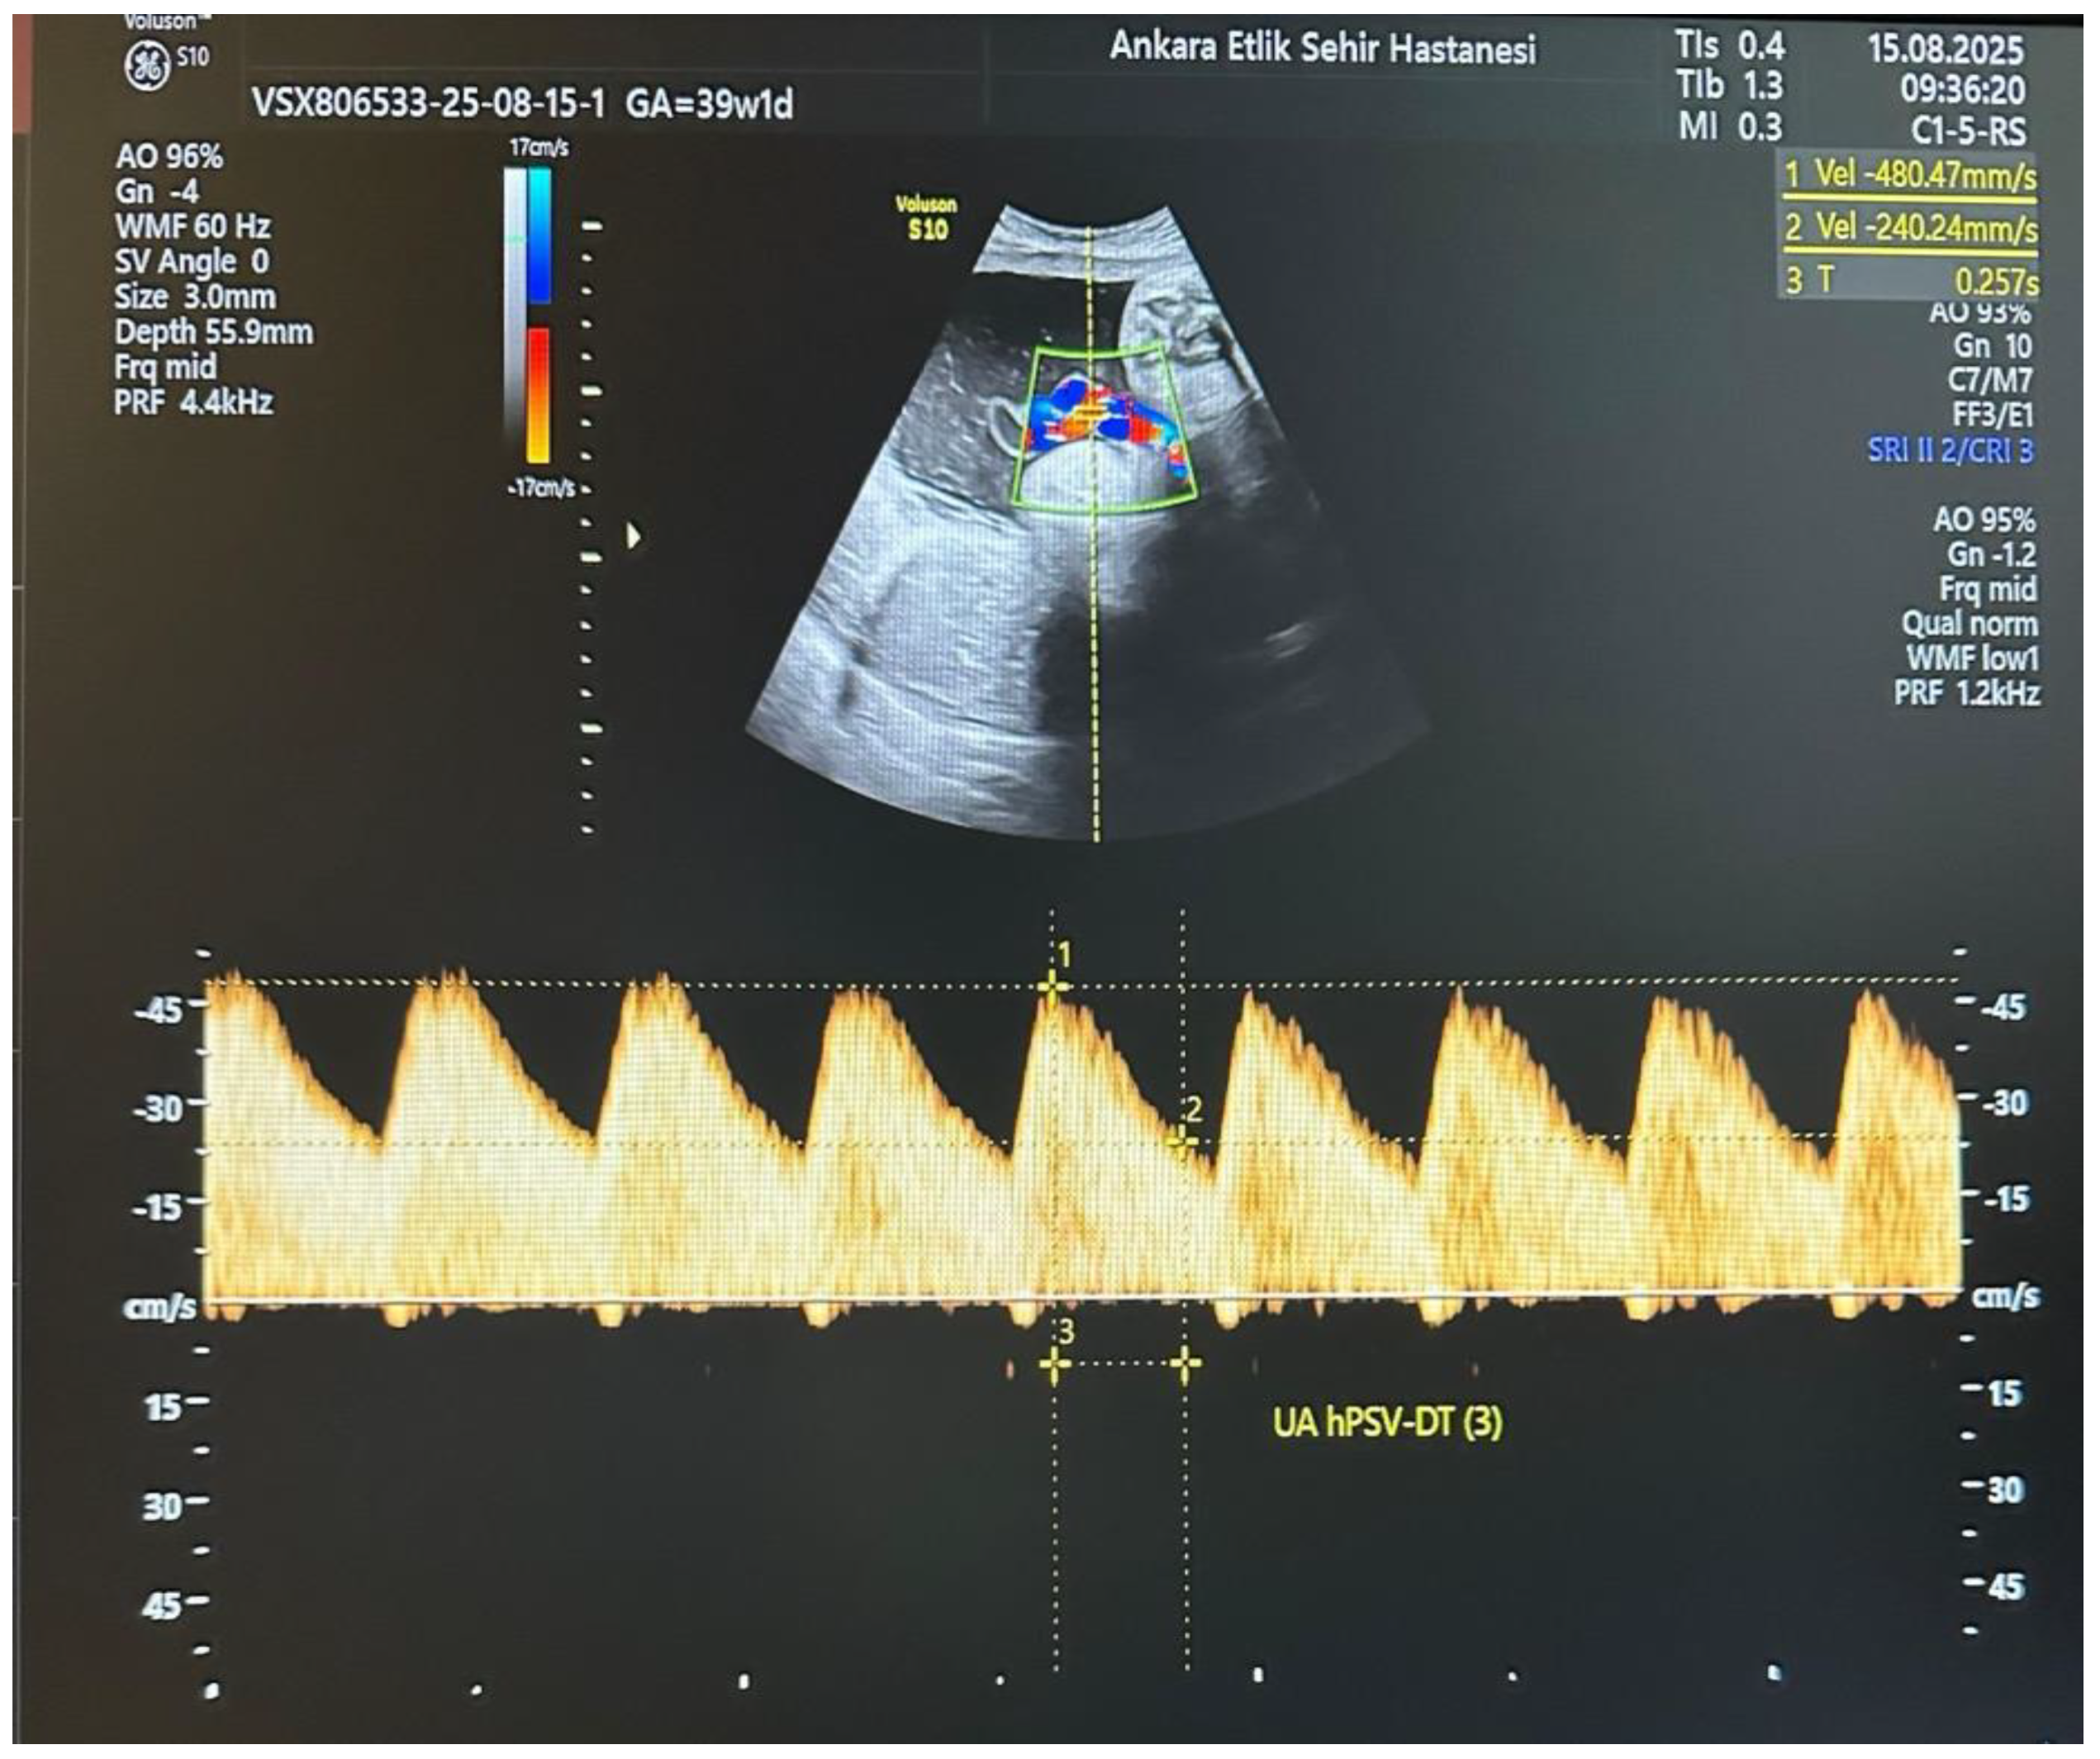

All participants underwent detailed ultrasound and Doppler examinations using a Voluson E10 system (GE Healthcare, Zipf, Austria) with a 2–6 MHz convex transducer. All measurements were performed by a single experienced perinatologist using a standardized protocol. The operator was blinded to maternal metabolic parameters (HbA1c, OGTT results, treatment type) at the time of Doppler assessment. Umbilical artery (UA) Doppler waveforms were obtained from a free-floating cord loop during fetal quiescence and in the absence of fetal breathing movements, ensuring an insonation angle < 30°. The UA hPSV-DT measurement was performed as described by Bustos JC et al. [10]. On the selected UA waveform, the first caliper was placed at the peak systolic velocity, and the second caliper at the midpoint between the baseline and the peak velocity. A straight line was then drawn from the second caliper to intersect the spectral envelope, and the time interval between these two points was measured in milliseconds (Figure 1). This process was repeated for three consecutive uniform waveforms, and the average value was used for analysis. An UA hPSV-DT value below the 5th percentile for gestational age, according to the nomogram by Bustos JC et al., was considered abnormal. Standard UA Doppler indices, including pulsatility index (PI) and systolic/diastolic ratio (S/D), were also recorded, along with uterine artery (UtA) and middle cerebral artery (MCA) Doppler parameters.

Figure 1. Umbilical artery half peak systolic velocity deceleration time (UA hPSV-DT): a novel Doppler parameter for prediction of adverse perinatal outcomes in pregnancies complicated by gestational diabetes mellitus. Measurement of the umbilical artery half-peak systolic velocity deceleration time (UA hPSV-DT) from a free-floating loop of the umbilical cord at 39 + 1 weeks of gestation. The Doppler insonation angle was kept below 30° during fetal quiescence without breathing movements. The calipers were placed at the peak systolic velocity and at half of this peak, and the time interval between these points was recorded in milliseconds according to the method of Bustos et al.